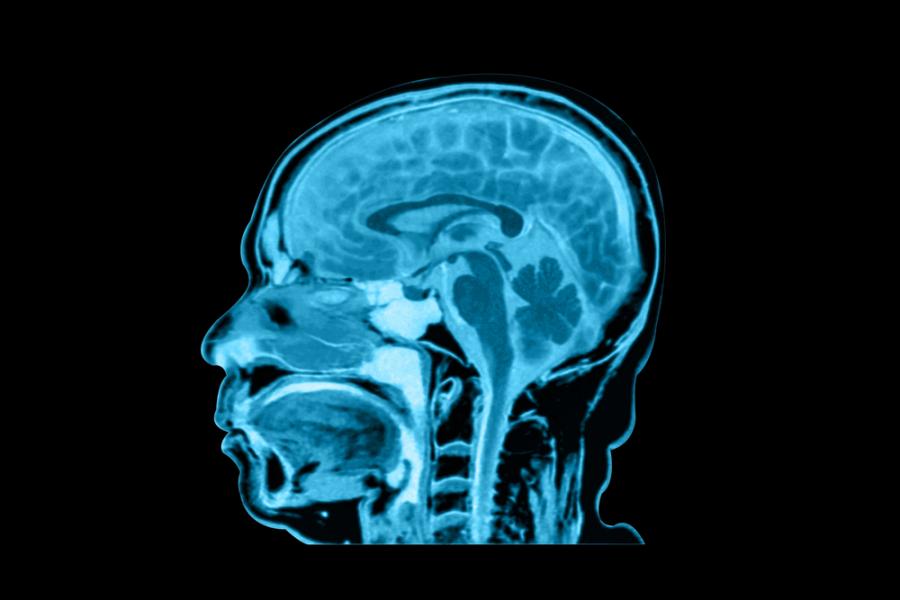

По-младите поколения имат по-голям мозък. Това по-здравословно ли е?

Според ново изследване размерът на човешкия мозък вероятно се увеличава постепенно с течение на времето, което може да намали риска от деменция при по-младите поколения.

Проучването е направило снимки на мозъците на повече от 3000 американци на възраст между 55 и 65 години и е установило, че родените през 70-те години на ХХ век имат 6,6% по-голям общ обем на мозъка от родените през 30-те години на ХХ век.

Членовете на поколението Х също така имат почти 8 % по-голям обем на бялото вещество и почти 15 % по-голяма повърхност на сивото вещество от членовете на мълчаливото поколение.

Една специфична част от мозъка, наречена хипокампус, която играе важна роля в паметта и ученето, е увеличила обема си с 5,7 % през последователно изследваните поколения.

"Изглежда, че десетилетието, в което е роден човек, оказва влияние върху размера на мозъка и потенциално върху дългосрочното му здраве", обяснява неврологът Чарлз ДеКарли от Калифорнийския университет в Дейвис, който е ръководител на изследването.

Тенденции при поколенията по отношение на вътречерепния обем на мозъка и обема на хипокампа. (DeCarli et al., JAMA Neurology, 2024)